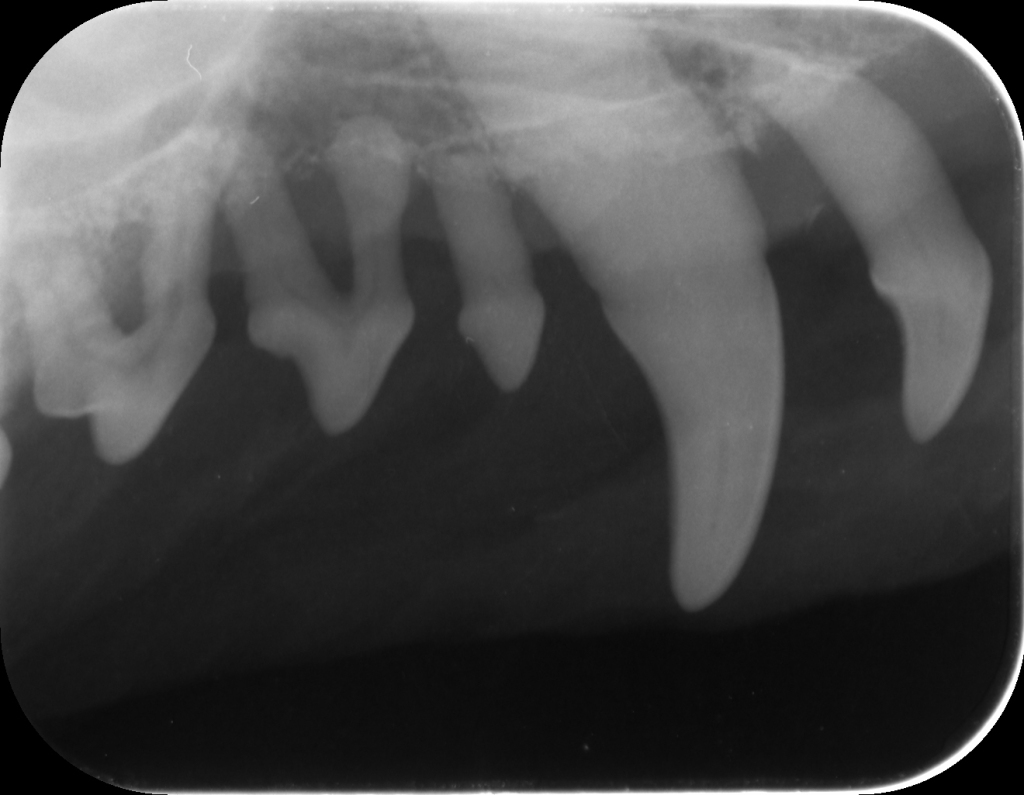

Eläinlääkärin suorittamassa hammashoidossa koiran hampaat puhdistetaan ensin plakista ja hammaskivestä. Hammastarkastus koettimen ja ientaskumittarin avulla päästään tekemään, kun hampaat ovat puhtaat. Hammastarkastuksen perusteella hampaista voidaan vielä ottaa röntgenkuvia diagnoosin tarkentamiseksi ja jatkohoidon suunnittelua varten. Koiran hammashoito edellyttää aina nukutusta, sillä hammaskivenpoistossa on päästävä puhdistamaan myös ientaskut. Lisäksi viimeisten hampaiden tarkastaminen on mahdotonta hereillä olevalla koiralla.